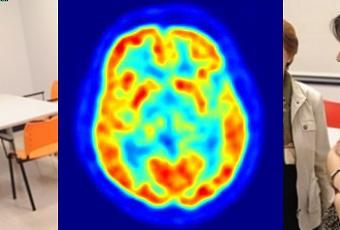

Identifican variantes genéticas asociadas a la enfermedad de Alzheimer

MADRID, 4 Abr. Europa Press -. Dos estudios de las universidades de Pensilvania en Filadelfia (Estados Unidos) y Cardiff en Reino Unido respectivamente han conseguido identificar cinco nuevas variantes genéticas asociadas con la enfermedad de Alzheimer. Los trabajos se publican en la edición digital de la revista 'Nature Genetics'.La enfermedad de Alzheimer, la forma más común de demencia, es un trastorno neurodegenerativo con una alta prevalencia entre los mayores.

Los científicos, dirigidos por Gerard Schellenberg desde Estados Unidos, informan de un estudio de asociación amplia de genoma sobre la enfermedad de Alzheimer en su inicio avanzado que incluyó a 8.309 casos y 7.366 controles cognitivamente normales.El equipo de Julie Williams desde Reino Unido combinó análisis de cuatro estudios de asociación amplia de genoma sobre la enfermedad publicados con anterioridad.A través de los análisis de replicación en los grupos de datos combinados y adicionales, ambos estudios en conjunto informan de cinco nuevas localizaciones asociadas con la enfermedad de Alzheimer.Esto eleva a 10 el número de localizaciones de susceptibilidad confirmadas para la enfermedad de Alzheimer y en conjunto incluyen genes candidatos con implicaciones en el funcionamiento inmune, procesos en las membranas celulares y el procesamiento de los lípidos.Los trabajos así subrayan mecanismos moleculares que podrían estar implicados en la neurodegeneración y la eliminación en el cerebro del amiloide beta, el principal constituyente de las placas amiloides que se forman en el cerebro y que caracterizan a la enfermedad de Alzheimer.Sigue a Europa Press Salud en Twitter: @EP_SaludSomos información